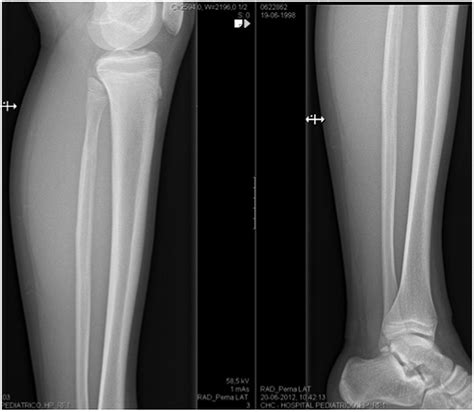

Diagnosis of Proximal Fibula Fracture

Diagnosing a Proximal Fibula Fracture involves a combination of physical examination and imaging tests. The diagnostic process typically includes:

• Physical examination: A healthcare provider will assess the injured area for pain, swelling, and deformity.

• X-rays: Imaging tests to visualize the bone and determine the location and severity of the fracture.

• CT scans or MRI: In some cases, more detailed imaging may be required to assess the extent of the injury and plan treatment.